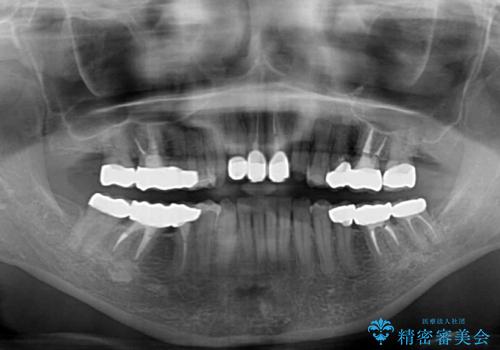

歯冠長延長術を行ったことで、自然な形態かつ清掃性の高いセラミッククラウンを装着することができました。

全顎的に治療を行ったため、治療期間も費用も負担は大きくなりましたが、統一感のある仕上がりとなりました。